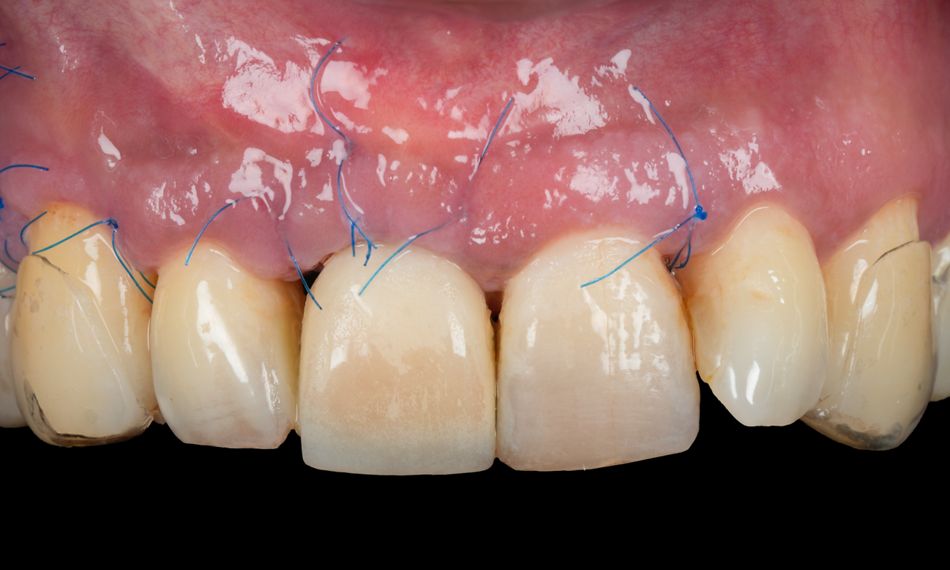

To further enhance the soft tissue profile and improve long-term peri-implant tissue stability, a connective tissue graft was harvested and placed over the augmented site. This graft contributed to an increase in mucosal thickness and supported wound closure, promoting favorable esthetic and functional outcomes (Figs. 15-17).

The surgical site was carefully sutured to achieve primary closure with tension-free adaptation of the flap. Postoperative care instructions were provided, and a control periapical X-ray was taken. The patient was scheduled for close follow-up to monitor healing progress (Figs. 18-20).

Two weeks later, the sutures were removed, and wound healing was satisfactory (Fig. 21).

Fig. 21

Three months postoperatively, the Maryland bridge was removed. The soft tissue healing was satisfactory (Figs. 22-24).